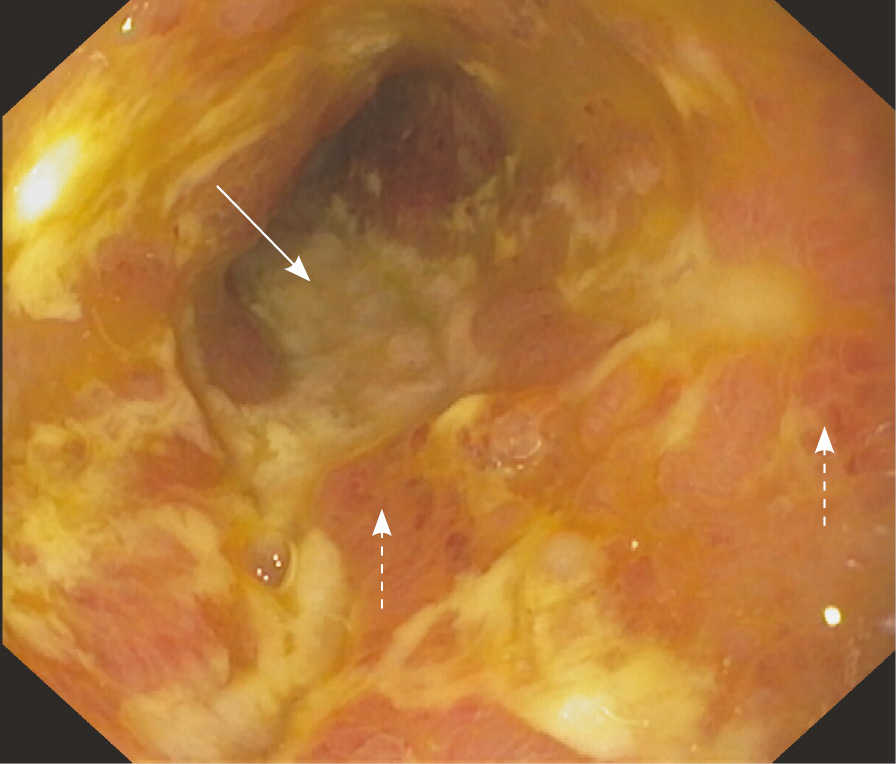

В начале февраля 2021 г. терапия адалимумабом была отменена, 17.02.2021 инициирована терапия канакинумабом 150 мг 1 раз в 4 недели подкожно и снижена доза колхицина до 1,5 мг в сутки. На этом фоне пациент отметил полное прекращение атак ССЛ. После отмены адалимумаба через несколько месяцев стали рецидивировать эпизоды динамической кишечной непроходимости. Пациент отказывался от проведения хирургического лечения и в течение последующих 2 лет продолжал наблюдаться у гастроэнтеролога. Периодически на фоне болевого синдрома в анализах отмечалось повышение СРБ. Получал курсами метронидазол, преднизолон внутривенно, с временным положительным эффектом. Продолжалась также терапия канакинумабом 1 раз в 4 недели с полным контролем атак ССЛ. В апреле 2022 г. выполнена энтероскопия, выявлены единичные эрозии проксимального отдела подвздошной кишки, множественные язвы терминального отдела подвздошной кишки, стриктура илеоцекального клапана (рис. 2). Пациент согласился на оперативное вмешательство.

Рис. 2. Энтероскопия от 08.04.2022: множественные сливающиеся эрозии и язвы под фибрином (сплошная стрелка), участки гиперемии слизистой оболочки в терминальном отделе подвздошной кишки (пунктирные стрелки)